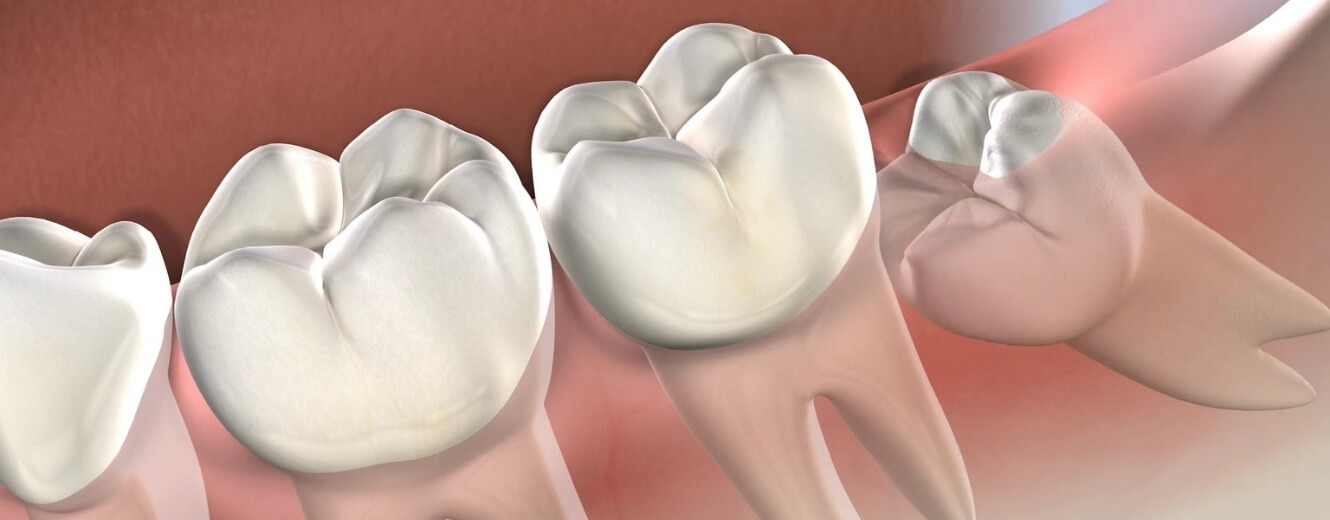

Gömülü 20’lik diş, çıkması gereken pozisyonda yeterli alan bulamayan veya yanlış açıda büyüyen üçüncü azı dişidir. Diş etinin ya da çene kemiğinin altında kalmış, kısmen çıkmış veya tamamen gömülü kalmış olabilir. Bu durum yalnızca lokal ağrıya neden olmakla kalmaz, aynı zamanda diğer dişlere baskı yaparak diş hizasında bozulmalara yol açar.

Gömülü dişin varlığı genellikle röntgenle tespit edilir. Bazı bireylerde hiçbir belirti vermezken, bazı durumlarda belirgin ve rahatsız edici semptomlarla kendini gösterir.